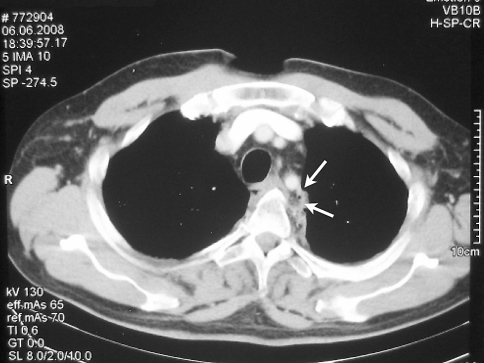

Fig. 3.

Initial computed tomography of the chest. Except for small collections of free air in the peri-oesophageal tissues that were not interpreted adequately during initial survey, there are no other injuries visible